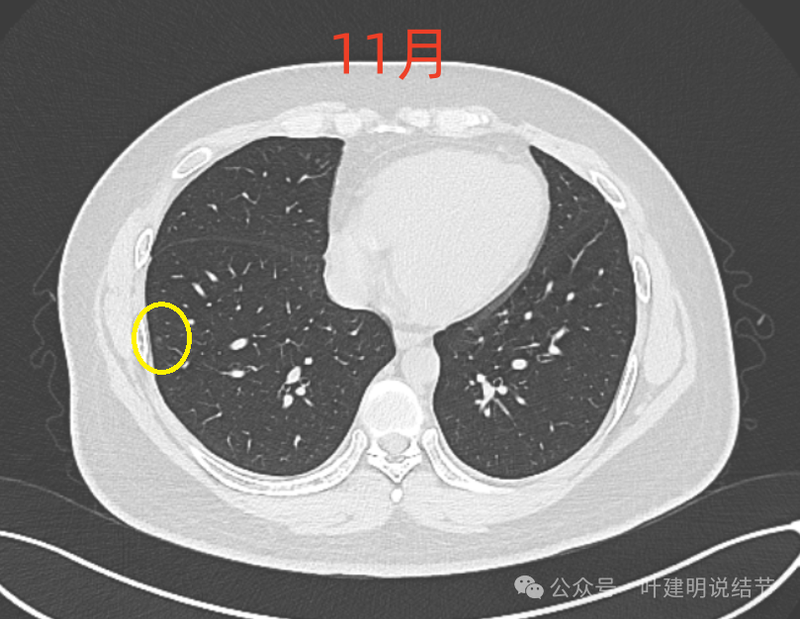

右肺尖磨玻璃结节,整体轮廓与边界清,有微小血管进入与穿行,但肿瘤本向说不上实性密度。

8月时似乎略模糊点,但显著的变化显然仍是说不上的。风险并不能算高,当然东西是肿瘤范畴的,原位癌或不典型增生均可能。

这样的对比,似乎略有变化,又似乎说不上明显变化。本身扫描条件也可能不同。所以我常强调,不要在意过于细微的变化,因为这不影响临床决策。而影响到决策的变化一眼就看出来了。有些同道呀,喜欢拿放大镜看,然后告诉患者有进展,很危险,得尽快手术!只能呵呵了。下面是不同指南与共识对于随访的建议,大家可以自己看。

现在的人工智能辅助诊断系统太过敏感,非常微小的结节都给你找出来,但是对于临床来说并没有多大意义。当结节才几个毫米的时候,既没有办法明确到底是什么,也没有必要明确到底是什么,按照中华医学会肺癌诊疗指南,8毫米以下纯磨玻璃结节或5毫米以下实性结节(包括混合密度结节实性成分不足5毫米)也就是年度复查就可以。所以其实并不一定要在意到底有多少处结节,或者要考虑是什么。主要就关注最主要的病灶,如果主病灶仍没有风险可以年度体检复查,那就可以随访,不能也不必有过大的思想顾虑。我看了你的CT,目前这些结节均风险小,其中右侧桔色框起来的是所谓主病灶,仍是纯磨密度,又还小,考虑不典型增生可能性较大;左下桔色的也是磨玻璃密度,但轮廓不如右上这处清楚,若确实肿瘤范畴,也是原位癌或不典型增生可能性大,但也有少许慢性炎伴肺泡上皮增生或纤维增生的可能性;中叶绿色的密度过高,更符合良性些;右下黄色的过小,11月份的像磨玻璃密度,边界较清,但对比8月时的,此灶不太明显,当然本身过小,也可能没有扫到最明显层面,不过总归风险小,能观察随访(左下的也8月时更显淡和不明显点)。总体上,这几处病灶都是风险还低,可以继续半年到一年复查随访,真若有明显进展并具有一定的风险再来干预处理不影响预后。本身年纪轻,又是多发结节,目前的病灶又都风险低,可以过于积极赶紧处理。意见供参考!